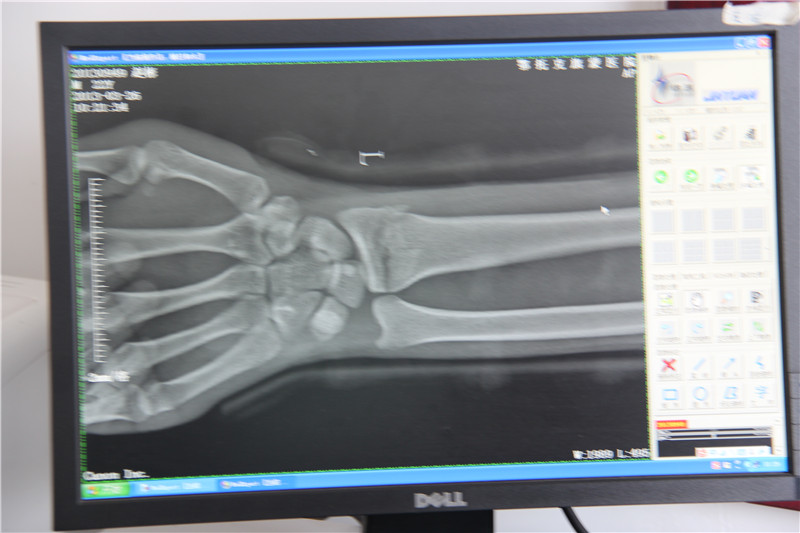

分布区域:鄂尔多斯全域照片说明:鄂尔多斯蒙医传统按摩法 摄影者:敖特根毕力格 时间:2013年3月26日..jpg鄂尔多斯蒙医传统按摩法照片说明:鄂尔多斯蒙医正骨术籍文献 摄影者:敖特根毕力格 时间:2013年3月26日.jpg鄂尔多斯蒙医正骨术籍文献照片说明:鄂尔多斯蒙医正骨术教材 摄影者:敖特根毕力格 时间:2013年3月26日1..jpg鄂尔多斯蒙医正骨术教材照片说明:鄂尔多斯蒙医正骨术教材 摄影者:敖特根毕力格 时间:2013年4月9日.jpg鄂尔多斯蒙医正骨术教材照片说明:鄂尔多斯蒙医正骨术文献 摄影者:敖特根毕力格 时间:2013年3月26日..jpg鄂尔多斯蒙医正骨术文献 照片说明:鄂尔多斯蒙医正骨术药膜疗法 摄影者:敖特根毕力格 时间:2013年4月9日.jpg鄂尔多斯蒙医正骨术药膜疗法照片说明:蒙医传统正骨术陈列室 摄影者 敖特根毕力格 时间:2013年3月26日.jpg蒙医传统正骨术陈列室照片说明:人体骨骼结构图陈列 摄影者:敖特根毕力格 时间:2013年3月26日..jpg人体骨骼结构图陈列照片说明:手部骨折小夹板固定 摄影者:敖特根毕力格 时间:2013年3月26日.jpg手部骨折小夹板固定照片说明:通过鄂尔多斯蒙医正骨术治疗痊愈的X光片 摄影者:敖特根毕力格 时间:2013年3月26日..jpg通过鄂尔多斯蒙医正骨术治疗痊愈的X光片照片说明:小夹板固定治疗 摄影者:敖特根毕力格 时间:2013年3月26日.jpg小夹板固定治疗照片说明:以X光线为基础诊断骨折部位 摄影者:敖特根毕力格 时间:2013年3月26日..jpg以X光线为基础诊断骨折部位照片说明:治疗腿关节骨折 摄影者:敖特根毕力格 时间:2013年3月26日_副本.jpg治疗腿关节骨折照片说明:治疗脱臼 摄影者:敖特根毕力格 时间:2013年3月26日.jpg治疗脱臼照片说明:传承人获的锦旗 摄影者:敖特根毕力格 时间:2013年3月26日..jpg传承人获的锦旗